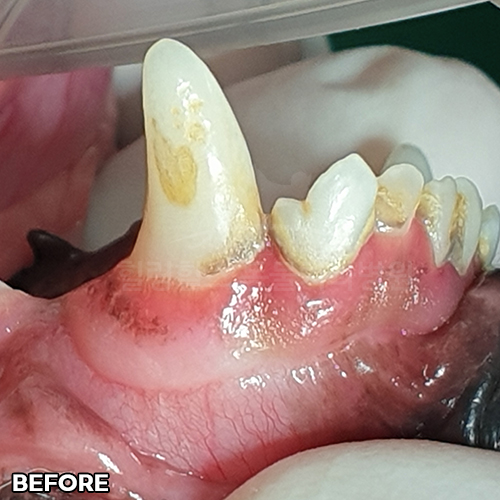

[강아지 치주염치료로 붉은 잇몸 호전]